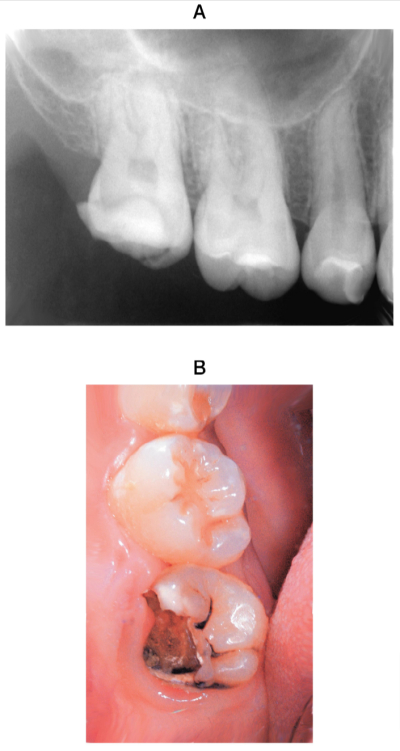

32 歳の男性。上顎右側第二大臼歯の自発痛を主訴として来院した。歯の保存が可能と診断し、麻酔抜髄を行うこととした。初診時のエックス線画像と修復物除去後の口腔内写真を別に示す。無菌的処置を行うために必要なのはどれか。2つ選べ。